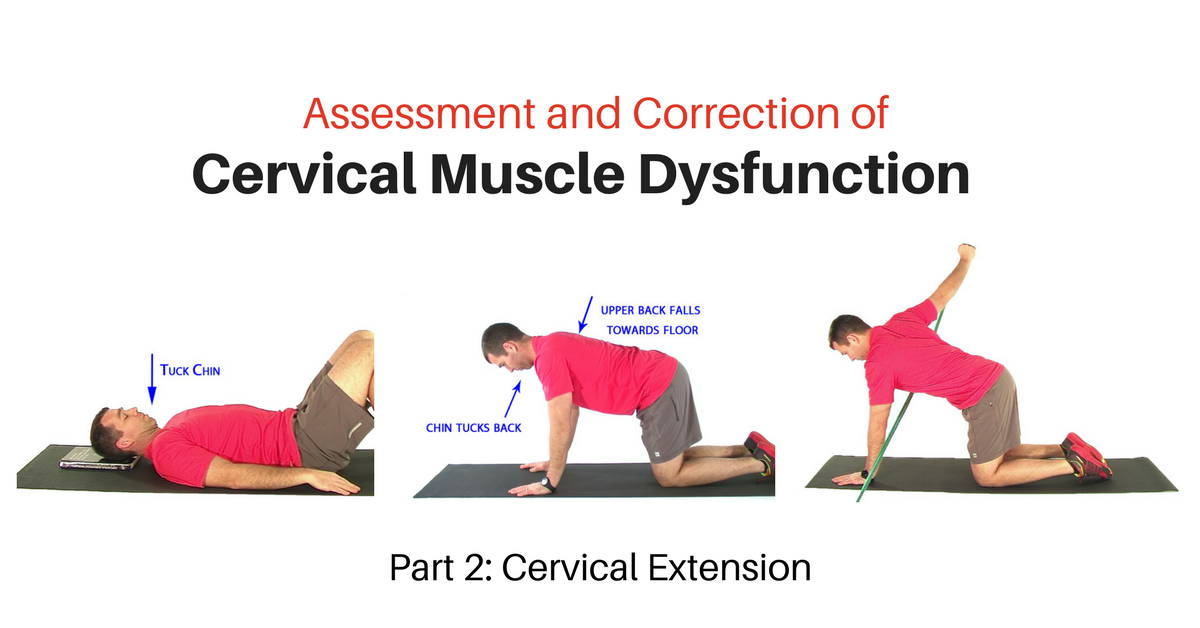

كيف نحسّن الإحساس بحركة الرقبة مع اعوجاج العمود الفقري؟

الخبر السار أن هذا الضعف يمكن تحسينه بالتدريب المنتظم. إليك أهم الطرق:

تمارين العلاج الطبيعي: تقوّي عضلات الرقبة وتحسّن التواصل بين الرأس والجسم.

التمارين أمام المرآة: تساعد المراهق على تصحيح ميل الرأس بنفسه بشكل واعٍ.

تمارين التوازن: مثل الوقوف على قدم واحدة أو استخدام لوحة التوازن تحت إشراف الأخصائي.

تصحيح الوضعيات اليومية: الجلوس المستقيم أثناء الدراسة واستخدام الهاتف بطريقة صحيحة يمنع الميل المزمن في الرأس.